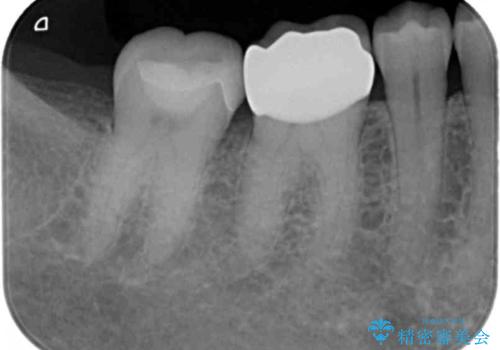

銀歯が取れた セラミックでのやり替え

- 右下奥歯の詰め物が取れたとのことで来院されました。

セラミックでの治療をご希望されましたが、残っている歯が少なかったためクラウンでの治療を行いました。

もう一つ奥の歯に関してもセラミックにやり替えたいとのことでしたので、こちらはインレーでの治療を行いました。

- 右下6:仮歯+セラミッククラウン/11,000円+110,000円 右下7:セラミックインレー/77,000円費用は治療当時の料金となります

残る歯が薄かったり、十分な量を確保できない場合はクラウンで治療した方が今後の破折リスクを抑えることができます。